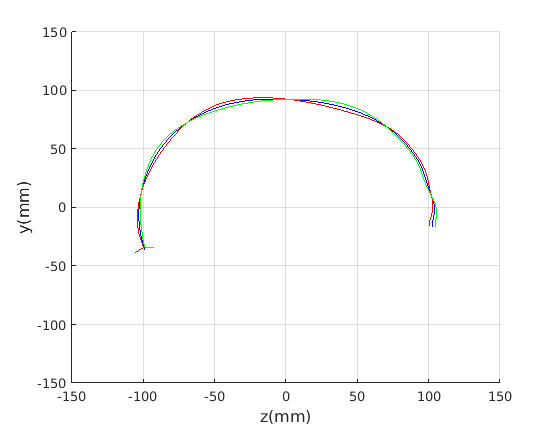

Figure 16 shows examples of the robust ellipse fit for four head profiles. The centre of the ellipse is used in a pose normalisation procedure where the ellipse centre is used as the origin of the profile and the angle from the ellipse centre to the nasion is fixed at -10 degrees. We call this Ellipse Centre - Nasion (ECN) pose normalisation and later compare this to GPA. The major and minor axes of the extracted ellipses are plotted as red and green lines respectively in Fig. 16.

|

Figure 17 shows all 100 profiles overlaid with the same alignment scheme. The median value of major ellipse axis and the ellipse centre-nasion angle differ by 3.6 degrees, so that when the nasion angle is fixed at -10 degrees, the median ellipse angle is -6.4 degrees (cf. -7.4 degrees with manual landmarking of the nasion). We noted regularity in the orientation of the fitted ellipse as is indicated by the clustering of the major (red) and minor (green) axes in Fig. 17 and the histogram of ellipse orientations in Fig. 18. For most people, the major axis of the ellipse is closely aligned with the y-axis (upright), and titled slightly forwards. A minority of heads (9%) in the training sample have their major ellipse axes closer to the vertical (these relatively tall and short heads are known as brachycephalic.) Ellipse axis clustering (relative to the fixed ellipse centre-nasion line) does not appear to be sharply defined. This is because many crania are close to circular in cross-section, making the orientation of these angles sensitive to small changes in shape from one person to the next. Note also the variation at the back of the head due to a variety of hair styles, some of which protrude from under the cap. We limit the region over which we model the cranial shape in order to crop this unwanted data out.